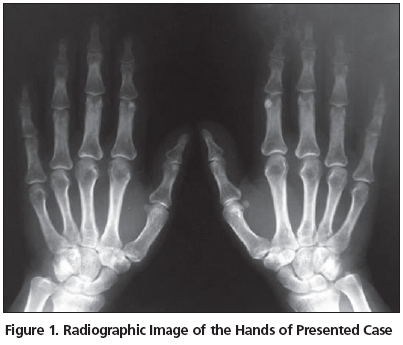

Forty eight years old female patient complaining of pain, swelling and warmth in her radio-carpal, MCP, PIP joints and ankles, accompanying morning stiffness lasting for one hour for 1 year applied to our outpatient clinic. Four years ago genetic analysis was made due to complaints of abdominal pain and fever attacks for 10 years. She was diagnosed as FMF after the detection of M694V homozygote mutation in her MEFV gene. She has been treated with 1.5mg/day colchicine for approximately four years. The family history was negative. Systemic examination of the patient was normal. Severity of pain was 8 cm (Visual Analogue Scale=VAS; 10cm), and in her musculoskeletal system examination tenderness and warmth were detected in her both wrists, all MCP and PIP joints and ankles. There were no deformities. Periarticular osteopenia and joint space narrowing were detected in all PIP joints in hand-wrist antero-posterior radiographies (Figure 1). The foot-ankle x-rays were normal. In laboratory examination, erythrocyte sedimentation rate (ESR) was 71mm/hr, C reactive protein (CRP) was 30mg/L, rheumatoid factor was 412 IU/ml, anti-CCP (cyclic citrullinated peptide) was positive. Following RA diagnosis, treatment with oral methotrexate 15mg/week and prednisolon 10mg/day was initiated. In addition to medical treatment, cold pack and Transcutaneous Electrical Nerve Stimulation (TENS) were applied to provide analgesia. Treatment with 1.5mg/day colchicine was continued for FMF. Patient was informed about her disease and regular control visits. During her control after two months her ESR and CRP were within normal limits, arthritis symptoms in her joints were regressed and VAS score for pain was 2. During the clinical follow-up patient described a decrease in her urination. She was then was referred to nephrology department and secondary amyloidosis was detected in her left kidney after biopsy.

As is known, initially and frequently involved regions in RA are the small joints of hands and feet[12]. While determining radiological characteristics of these regions, Larsen Dale Method can be utilized[13]. In our case, periarticular osteopenia and joint space narrowing were detected in all PIP joints in hand-wrist x-rays. According to Larsen staging this was compatible with stage 1 RA radiological image[13]. On the other hand arthritis occurring during the course of FMF affects particularly the large joints of lower extremities. In most cases temporary, monoarticular type, non-erosive and non-deforming arthritis was seen. In a study arthritis was found in 31% of FMF patients and monoarticular involvement was detected in 70%, oligoarticular involvement was detected in 26% and polyarticular (similar to rheumatoid) involvement was found in 4% of the patients[14]. During FMF course polyarticular type arthritis involving small joints is seen very rarely[15]. Attacks of arthritis generally regress in a week. But in 5% of the cases, prolonged attacks of arthritis involving particularly hip and knee can occur and causing permanent joint injury and deformities[16]. In our case, there was polyarticular type small joint involvement effecting hand and foot joints symmetrically, similar to joint involvement in RA. Laboratory examination in order to exclude RA in differential diagnosis showed RF and anti-CCP positivity. RF test is positive in 70-80% of RA patients[17]. However anti-CCP is a very recent and specific marker for RA. For the diagnosis of RA, specificity of Anti-CCP autoantibodies is 91-98% and sensitivity is 41-67%[18]. In addition to these laboratory findings, as she fulfilled American College of Rheumatology (ACR) criteria[19] by the presence of morning stiffness and radiographic findings, our patient was diagnosed as RA.